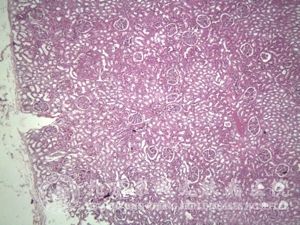

2、肾型。此种病情较为严重,发生率较高。它是由于肾小球毛细血管炎性反应而出现血尿、蛋白尿及管型尿的现象。在疾病的时期都会有出现肾脏症状的可能。但在一周之后较为常见。主要的表现为越早出现尿变化,肾炎就愈重。由于反复发作的病例,很容易引发慢性肾炎、肾病综合征,严重时肾功能会出现衰竭现象。通常称这种情况下的肾炎为过敏性紫癜性肾炎。